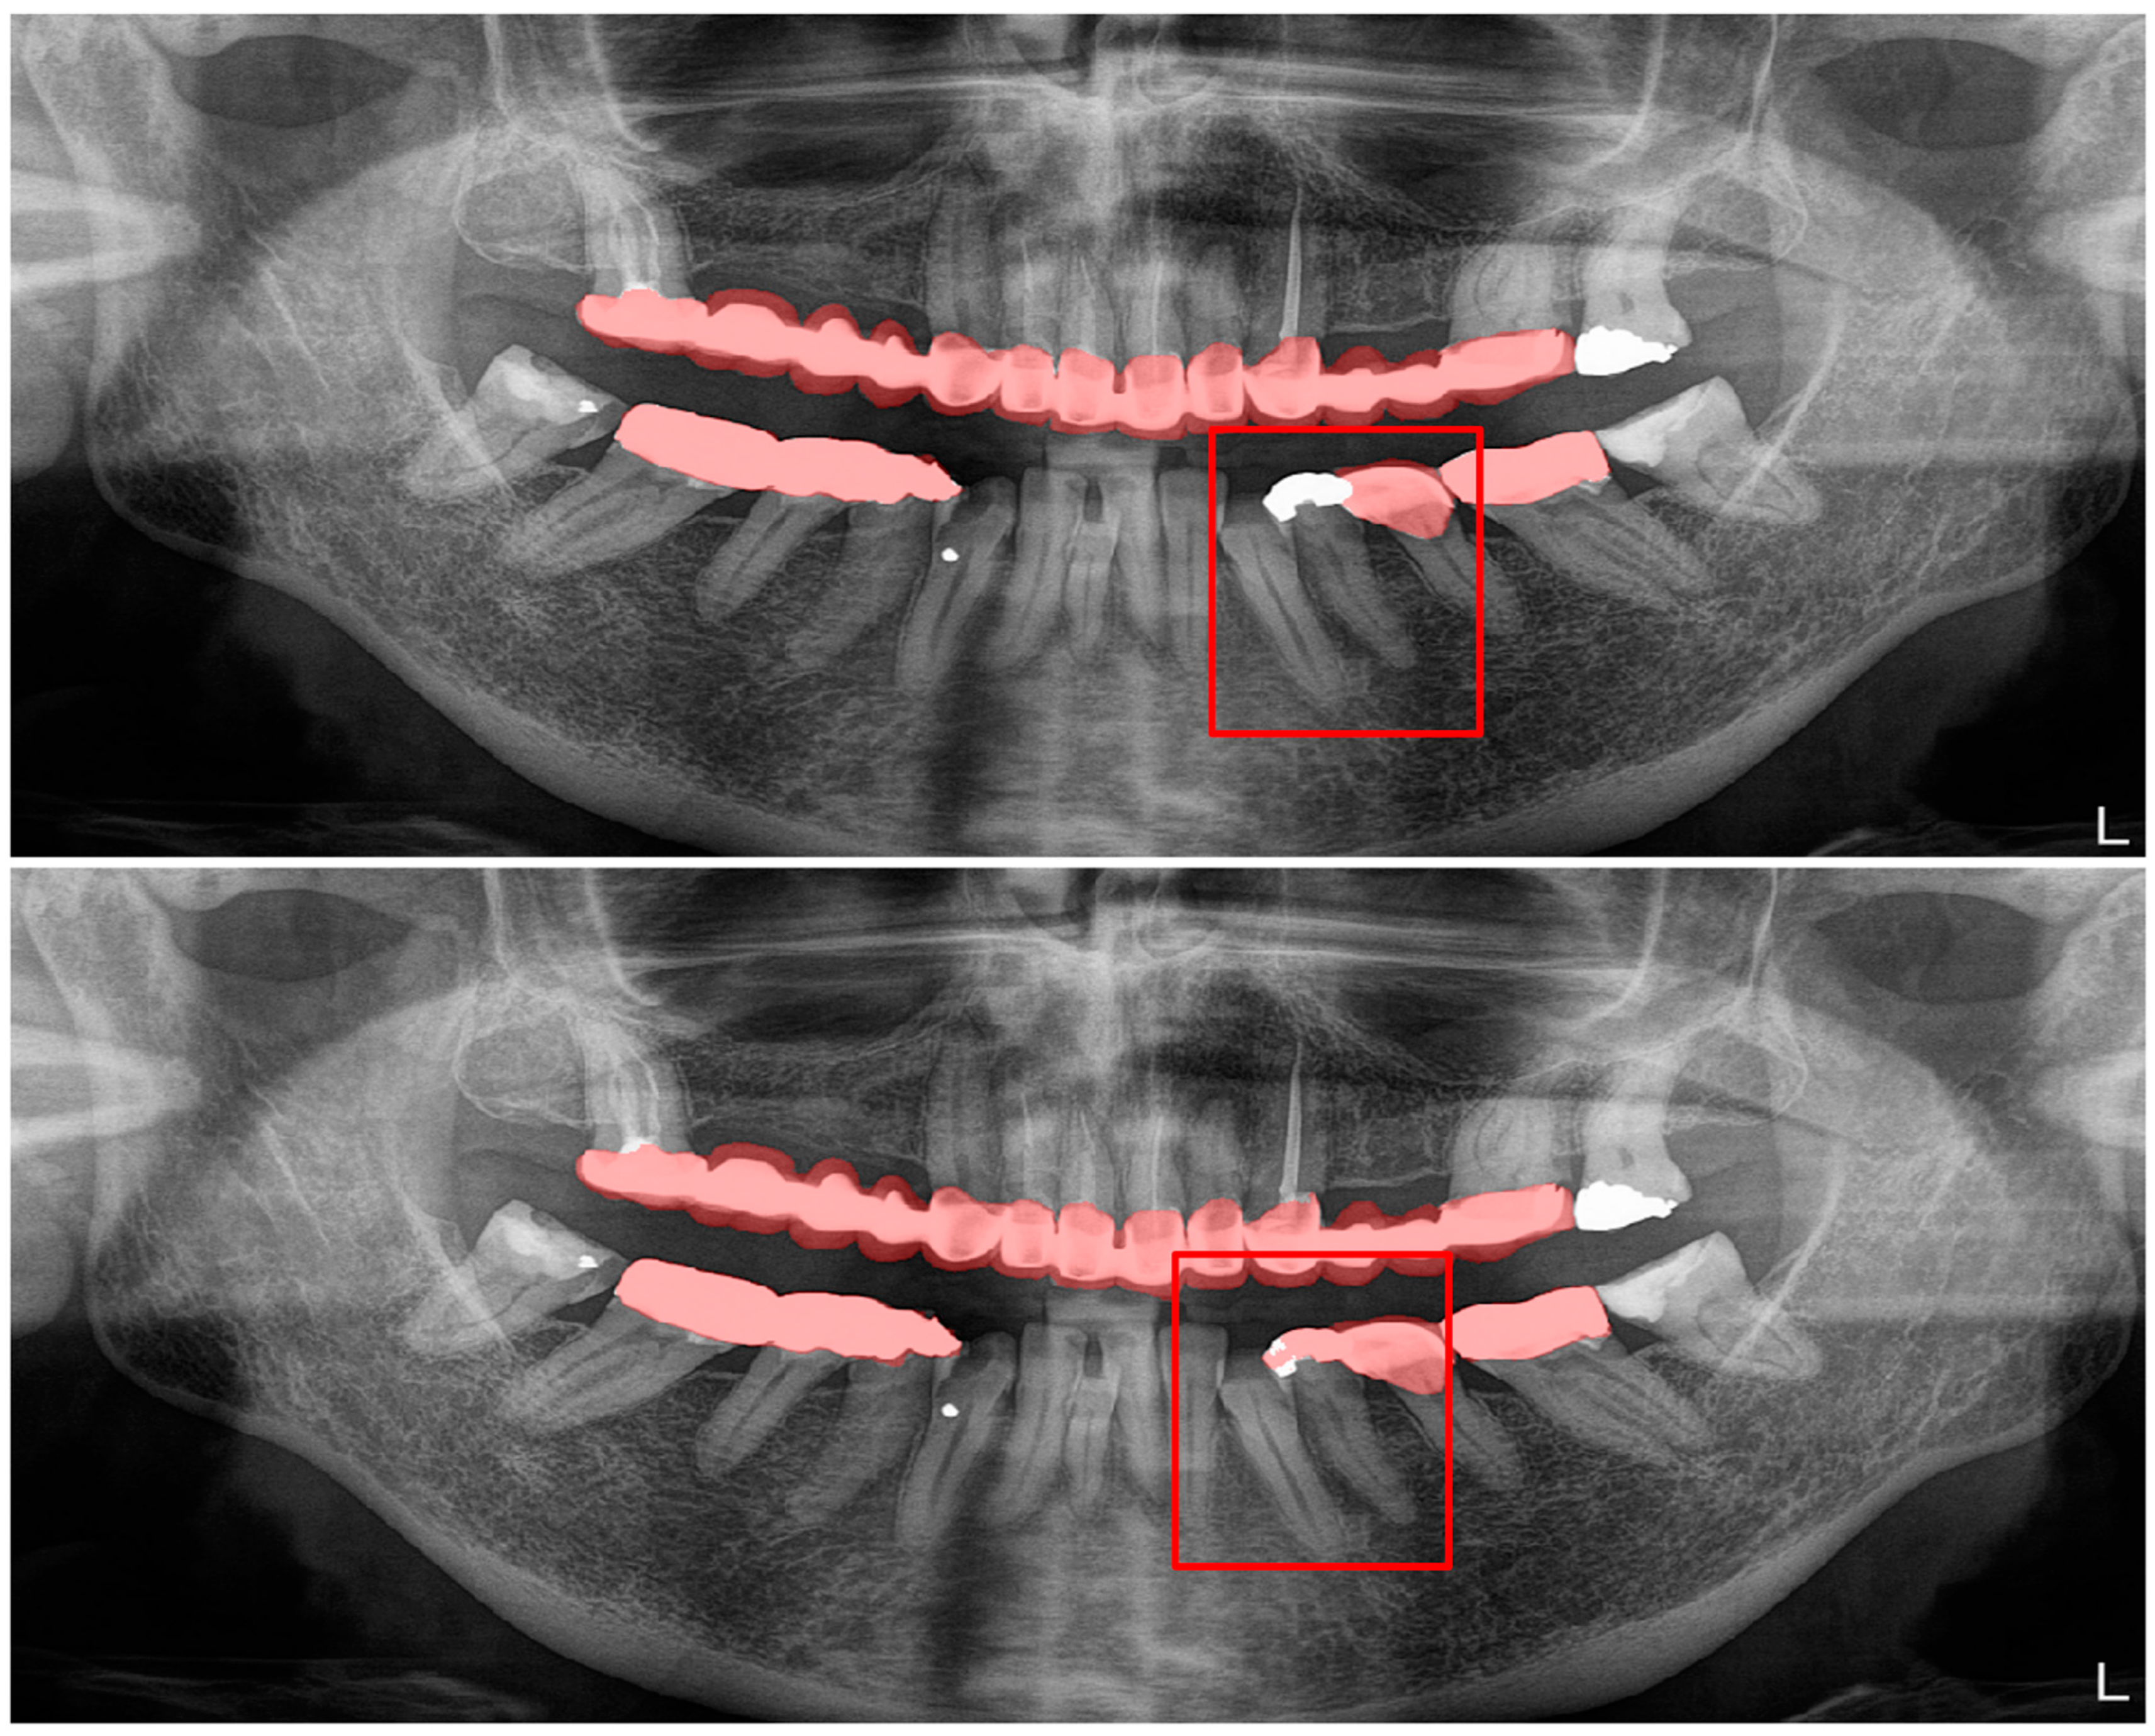

| Structure | DSC |

|---|---|

| Dental caries (Figure 3) | 0.88 |